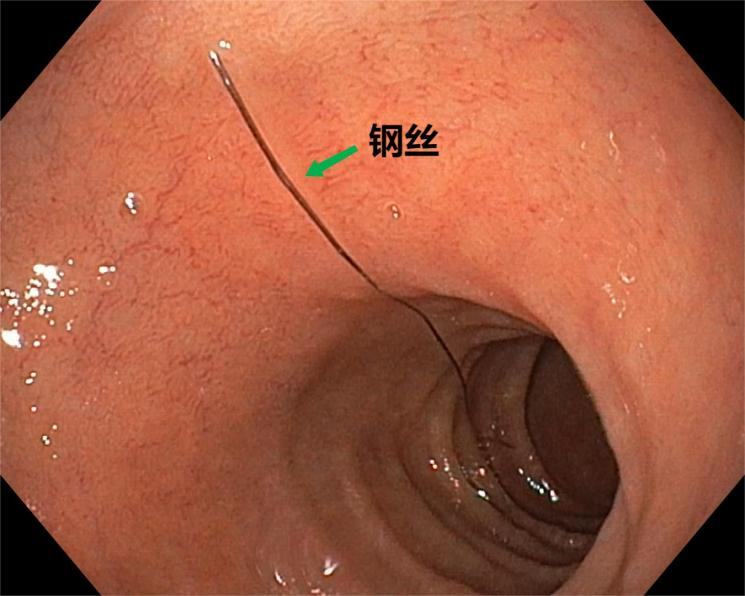

尖锐或不规则异物

如 鱼刺、枣核、首饰、针 等,容易划破消化道,甚至引起消化道出血、穿孔。

△尖锐的钢丝